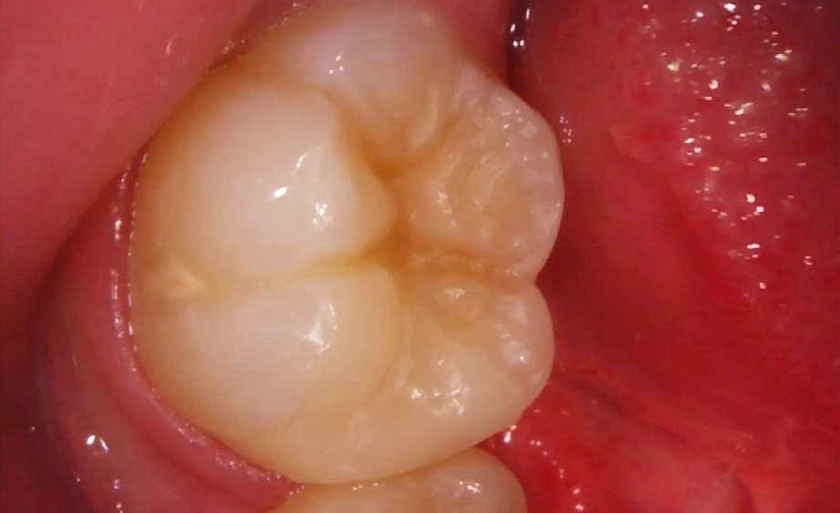

⑤白い詰め物で穴を埋めました(ダイレクトボンディング)自然な仕上がりになったと思います。

| 主訴 | 穴が空いているところを治したい |

| 治療内容 | VPT、ダイレクトボンディング |

| 治療期間・回数 | 1回 |

| 治療費 | 右下6番目VPT+ダイレクトボンディング66,000円(税込) |

| リスク・副作用 | 歯の神経が炎症を起こすリスクが低確率であり、歯の薄い部分が欠けるリスクが低確率であり。 |